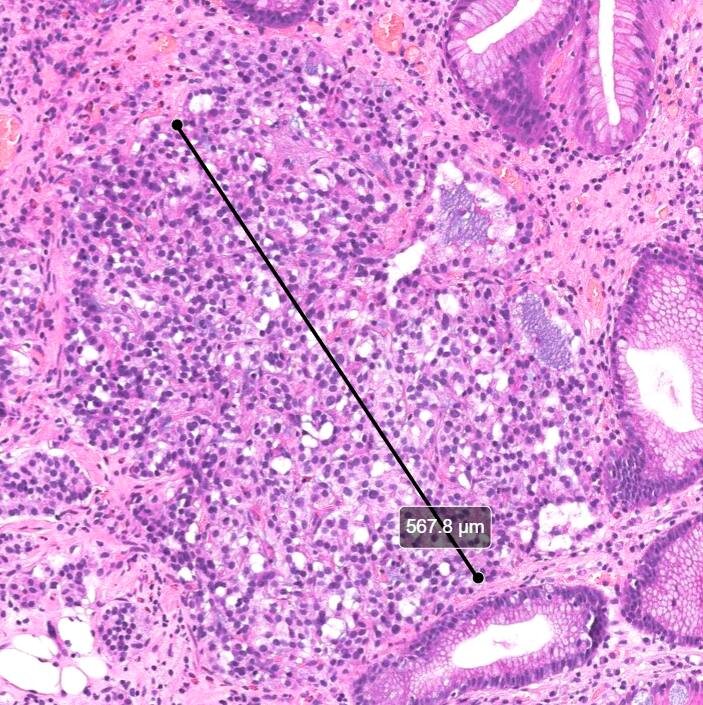

Гистофото НЭО 1 типа из предыдущего поста, любезно предоставлены Мариной Юрьевной.

Удалил обычными биопсийными щипцами, радикально. Необходимо индивидуально подбирать метод удаления в каждой конкретной ситуации. Главные критерии — радикальность и безопасность.

Здесь наглядно продемонстрировано, почему это образование НЕ подслизистое (субэпителиальное).